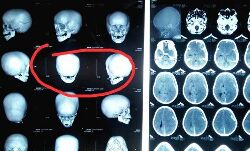

തൊടുപുഴയിലെ ക്രൂരത: ഏഴു വയസുകാരന്റെ ആരോഗ്യനിലയില് പുരോഗതിയില്ല; തലച്ചോറിന്റെ പ്രവര്ത്തനം നിലച്ചു

3 April 2019 3:05 AM GMTതലച്ചോറിന്റെ പ്രവര്ത്തനം പൂര്ണമായും നിലച്ച നിലയിലാണ്. ഒരാഴ്ച്ചയായി പൂര്ണമായും വെന്റിലേറ്ററിന്റെ സഹായത്തോടെയാണ് കുട്ടിയുടെ ജീവന്...